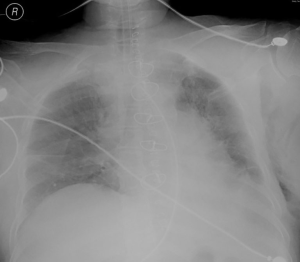

The patient failed to show signs for removal of tracheal intubation, and still required assisted breathing through a ventilator on September 30, 2019. A bedside chest X-ray showed a decrease in lung field transillumination and an increase in lung texture (Figure 3). Then anti-glucocorticoids and diuretic treatment were given for three consecutive days. The tracheal intubation was successfully removed on October 5, 2019. Postoperative recovery of the patient was good, and she was successfully discharged on October 7, 2019. Postoperative pathology showed well-differentiated liposarcoma and incomplete capsule. Immunohistochemical results are as follows: CK (−), VIM (+), Ki67 (3% +), SMA (−), CD34 (−), CD68 (−), S100 (+), CDK4 (+), MDM2 (−), P16 (+).The patient remained well and showed no sign of recurrence on March 10, 2020 (Figure 4). The timeline of the symptoms, treatment, and follow-up of this case is listed in Figure 5. All procedures performed in studies involving human participants were in accordance with the ethical standards of the institutional research committee and with the Helsinki Declaration (as revised in 2013). Written consent was obtained from the patient for publication of this case report.